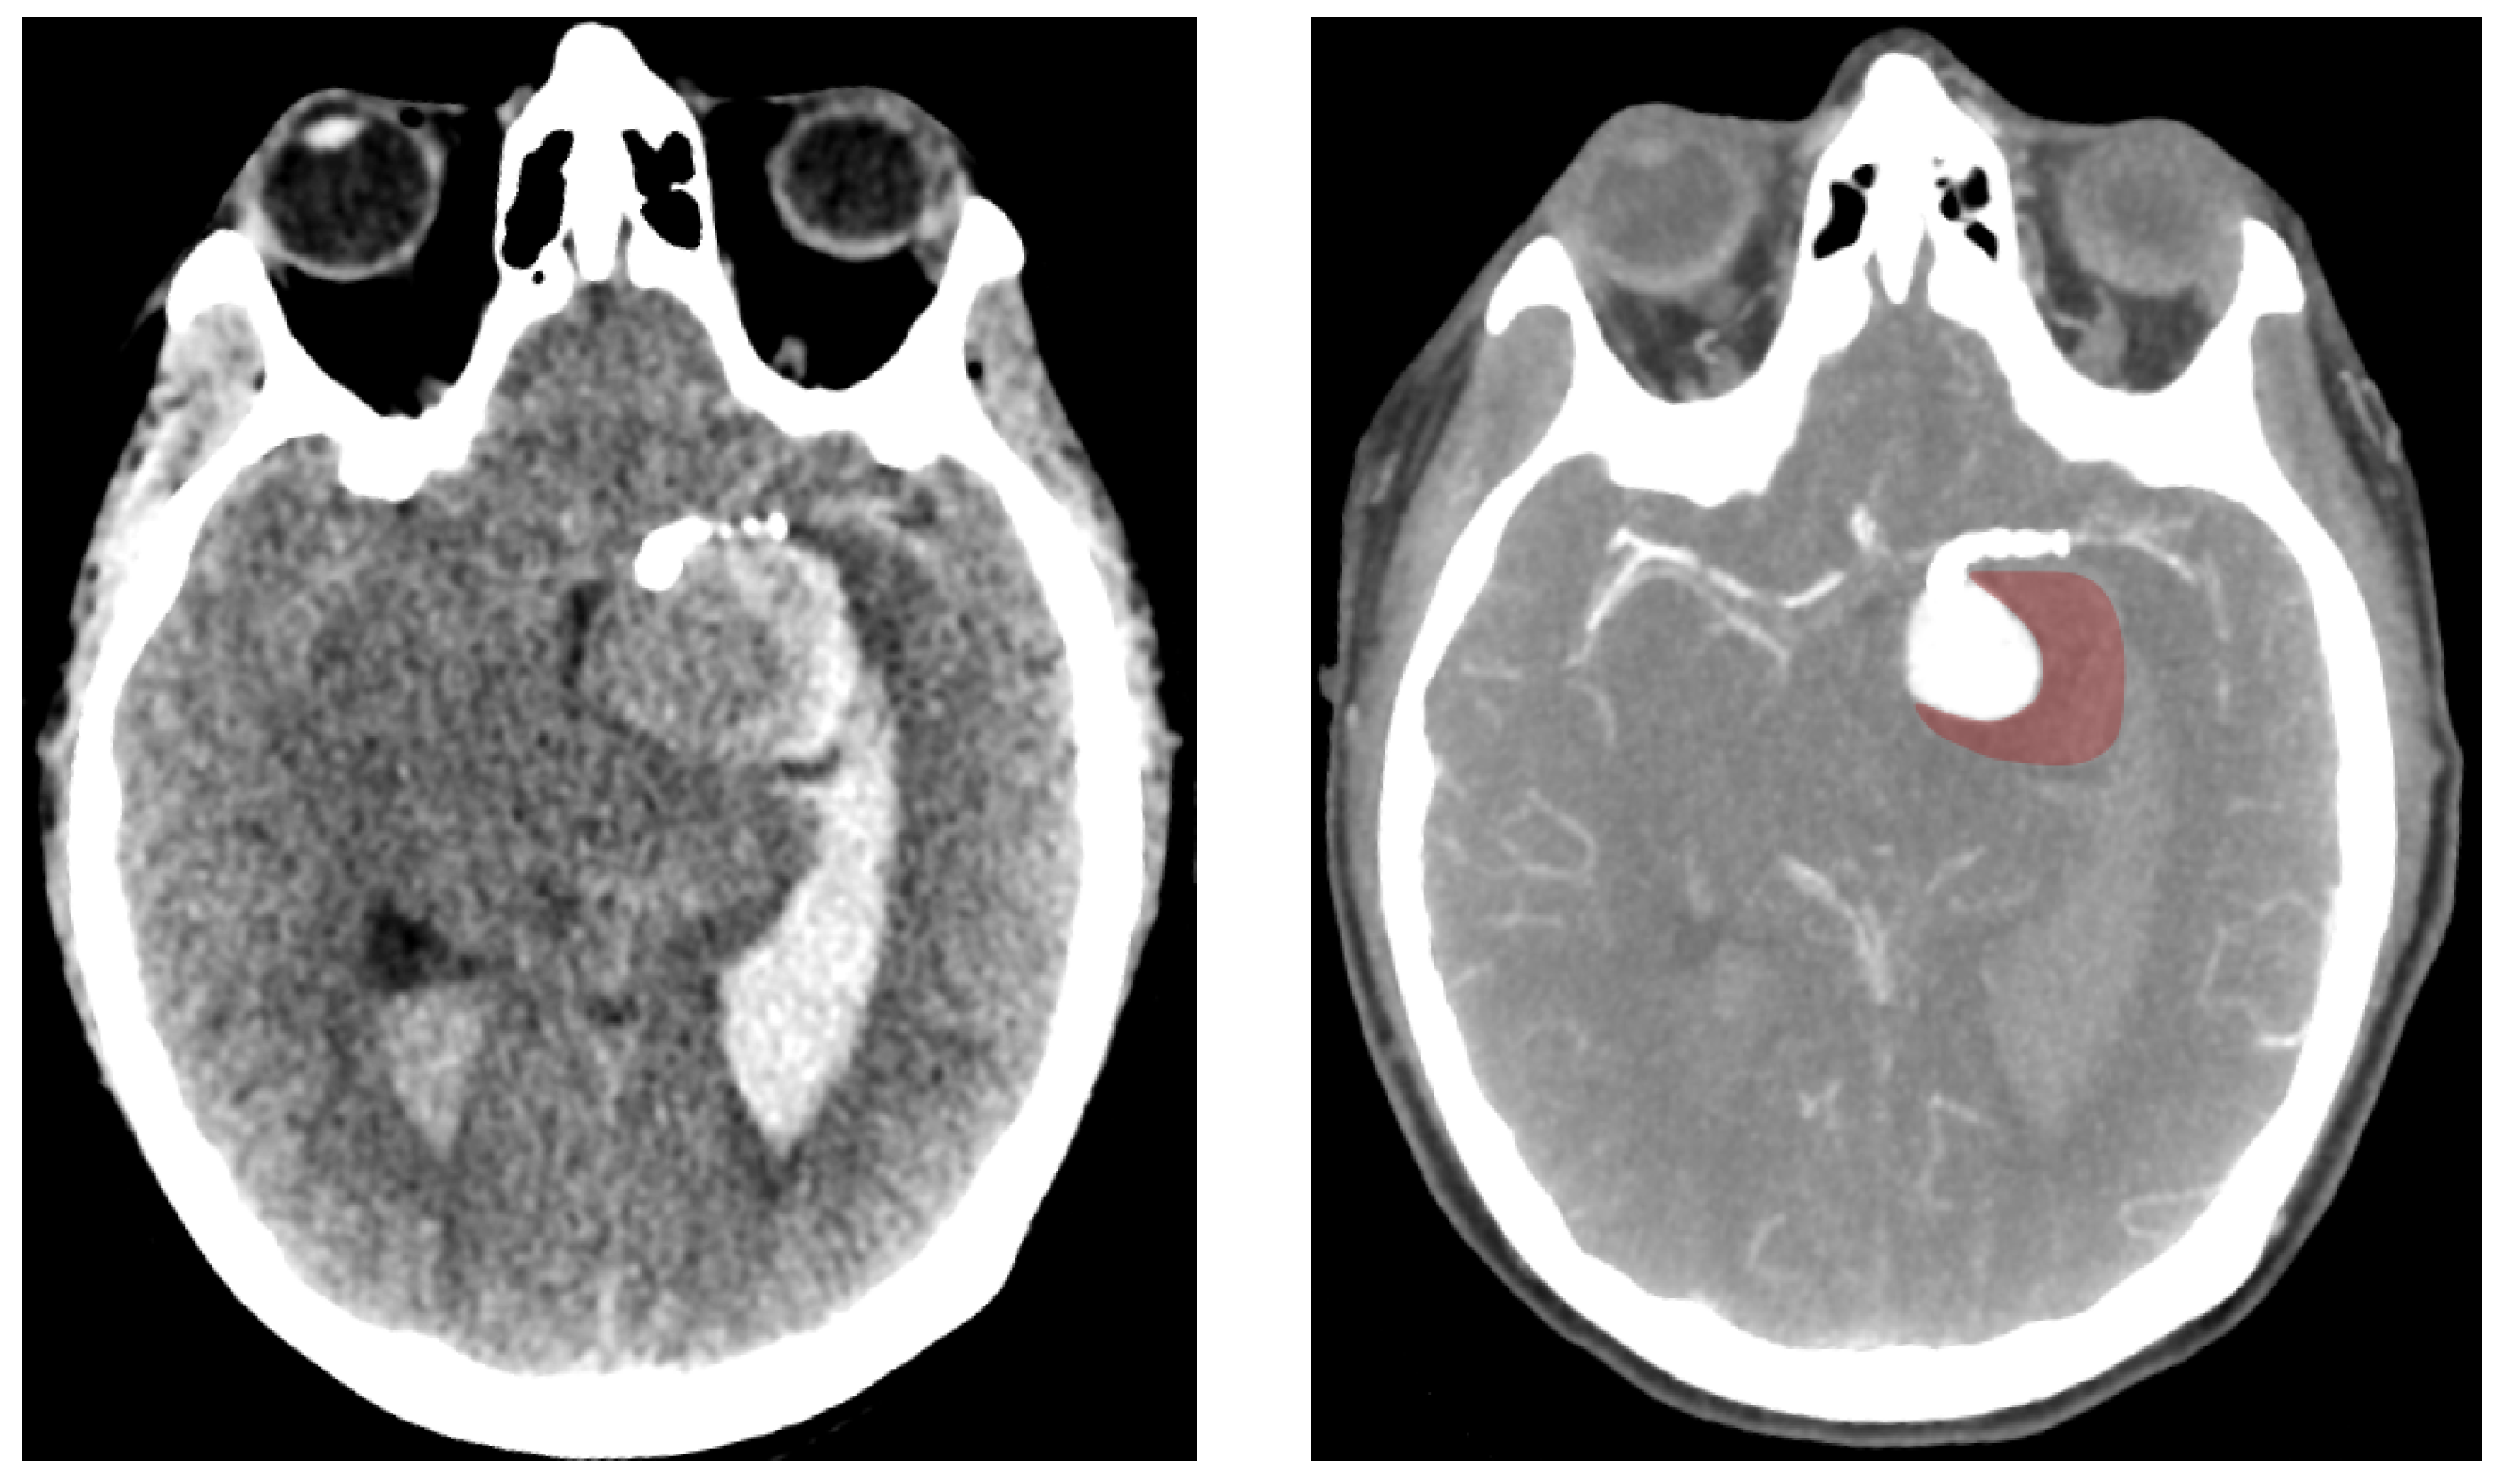

Eight months after the intervention, the patient reported a sudden headache. A Computed Tomography (CT) scan revealed spontaneous hyperdensity in the aneurysm, suggesting partial thrombosis. A week later, the patient suffered a sudden coma, with a Glasgow Coma Scale score of 4 caused by subarachnoid haemorrhage and a left temporal hematoma. Cerebral arteriography showed persistent aneurysm opacification, a patent stent, and active contrast leakage from the posteroinferior part of the aneurysm sac, marked in red on Figure 2. Rotational angiography (6 fps) revealed noticeable wall movement that could not previously be seen (see Figure 1). The coil deployment stopped bleeding and occluded the aneurysm, but did not prevent the patient’s death 5 days later.

In the present case of a giant aneurysm, thrombosis was suspected based on hyperdense regions observed on CT imaging (as seen in Figure 8), although no autopsy was performed to confirm it. Thrombosis was first noted one week before rupture and expanded significantly in the interim. These observations align with the disease progression described by Kulcsar et al. [9]. However, the question remains whether thrombosis alone could trigger autolysis rapidly enough to cause rupture within just a few weeks. Kulcsar’s study described a late rupture case where the aneurysm remained fully patent three months post-intervention, with no apparent changes. Twenty days after switching to single anti-platelet therapy, the aneurysm ruptured and was found to be largely thrombosed. If autolysis was indeed responsible for rupture in the cited case, it suggests that the fatal degradation process may require only a short period once initiated. Further studies dedicated to the thrombosis process could provide here valuable information regarding the degradation timeline.

Figure 8. Computed Tomography (CT) scan of the ruptured aneurysm (left) showing the presence of blood in both ventricles. On the (right), a CT scan using a contrast agent which highlights the arteries and the perfused sections of the aneurysm. The red-tainted section corresponds to the thombosed regions at which the rupture occurred.